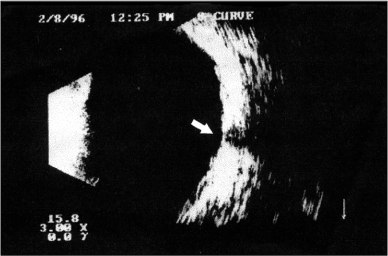

c) A flecha da figura 3, após edição, ficou deslocada. A figura corrigida aparece abaixo.